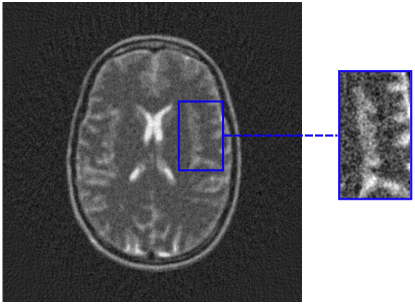

5 Benchmark procedure

To assess the performance of the HLSF, four phantoms with structural patterns of different complexity have been considered (Fig. 4). PH-1 in Fig. 4(a) is the segmentation of a reconstructed slice of mouse lung tissue at micrometer scale. PH-2 in Fig. 4(b) is a multilevel segmentation of a MRI scan of a human brain. PH-3 in Fig. 4(c) is a multilevel segmentation of a CT slice of a human lung. PH-4 is the well-known Shepp-Logan phantom [16].

Refer to caption

(b) PH-2

Figure 4: Set of simulated data used to benchmark the HLSF. PH-1 has 784 ×\times 784 pixels; PH-2 has 592 ×\times 592 pixels; PH-3 has 500 ×\times 500 pixels; PH-4 has 512 ×\times 512 pixels.

(a) FBP

(b) CFBP

Figure 8: Reconstructions performed by FBP and CFBP with Parzen filter of a PH-2 sinogram 82 views ×\times 592 pixels (SF = 9%) + Poisson noise with σ=2.8%𝜎percent2.8\sigma=2.8\% of the original sinogram mean value.